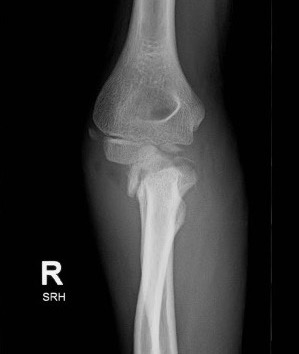

Radial neck fracture and olecranon fracture